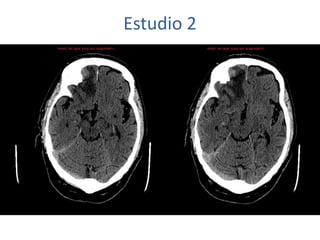

Estudio 2

• Estudio sin y con contraste, con reconstrucciones sagitales y coronales

del estudio con contraste.

Se observa una lesión ocupante de espacio en lóbulo frontal derecho que

presenta un tamaño de 18 x 32 x 22 mm (cc x ap x tr), bilobulada, no del

todo bien delimitada, con realce en anillo irregular, con hipocaptación

central, probablemente por necrosis, y asociada a un extenso edema

vasogénico con efecto masa tanto sobre los surcos de la convexidad

como sobre la cisterna insular, el sistema ventricular y la línea media,

esta última con un desplazamiento de 5 mm a la altura del septo

interventricular.

No se aprecian otras lesiones focales intra o extraaxiales de significación

patológica.

Habría que considerar como primera posibilidad que se tratase de una

lesión metastásica, por bien un tumor primario, aunque no se puede

descartar otras opciones, sin imprescindible correlación con la clínica y

con sus antecedentes.